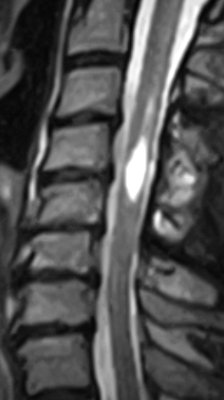

В дальнейшем для точной диагностики сирингомиелии проводят магнитно-резонансную томографию (МРТ). В тех случаях, когда более важна детальная визуализация костных структур или при наличии противопоказаний к проведению МРТ, может проводиться компьютерная томография (КТ) с миелографией. На КТ сирингомиелия будет выглядеть как области расширения спинного мозга, а на Миело-КТ будут видны заполненные контрастом полости на поздних изображениях.

МРТ считается более подходящим методом для визуализации структур нервной системы, поэтому данный вид диагностики наиболее предпочтителен. Магнитно-резонансная томография позволяет провести как оценку наличия и степени сиринкса, так и даёт возможность оценить пресиринкс – интерстициальный отек паренхимы спинного мозга, который не виден на КТ.

На МРТ сирингомиелия лучше всего визуализируется на Т2-взвешенных изображениях, на них видны продолговатые очаговые изменения спинного мозга, дающие яркий сигнал равный по интенсивности спинномозговой жидкости. На последовательности T2-Flair, на которой сигнал от свободной жидкости подавляется, полости с ликвором выглядят гипоинтенсивными (темными). На Т1-взвешенных изображениях области поражения имеют также гипоинтенсивный сигнал, то есть мы видим их темными. Форма полостей в спинном мозге может быть довольно сложной с перегородками. Участки центрального канала могут расширяться и могут связываться с полостями сиринкса. Продольную протяженность поражений оценивают на сагиттальных срезах, особенно T2-взвешенных изображениях, а ширину и высоту на – аксиальных срезах.

Рис. 2. МРТ шейного отдела позвоночника собаки. Сагиттальная и аксиальная проекции, Т2-ВИ изображения. Стрелками показана значительная сирингомиелия на уровне C1-С6.